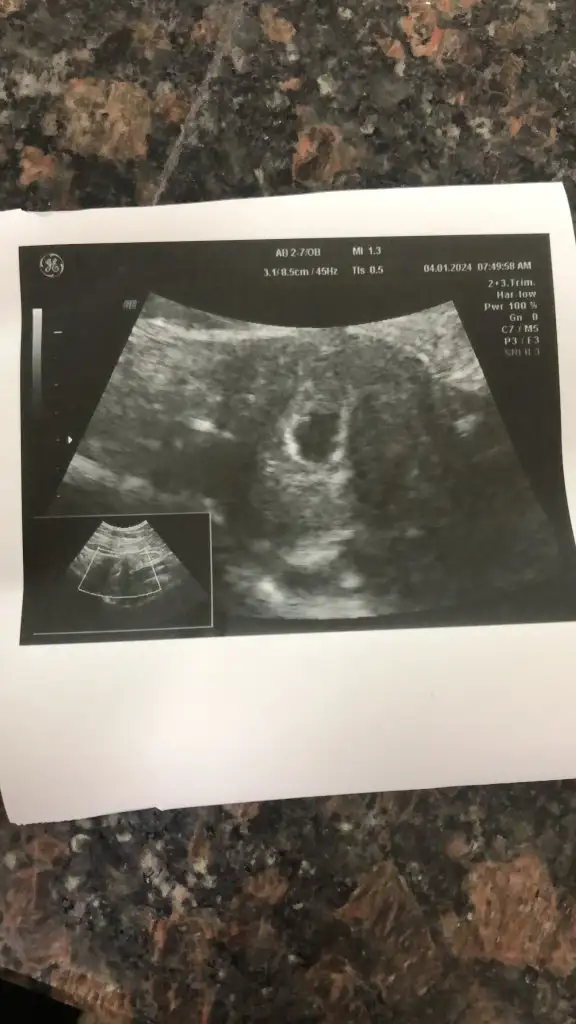

Selam canım evet 21 Aralık tı ben pazartesi günü gittim kontrole keseyi gördüm çok şükür ❤️ 2-3 hafta sonra kontrole gel dedi kalp atışı için gideceğim.. Ayy sen kalp atışını da duyarsın, o zaman gittiğinde inşallah 🐣🐣

Merhaba allah tamamına erdirsin🙏 kese görüntünüz var mı acaba